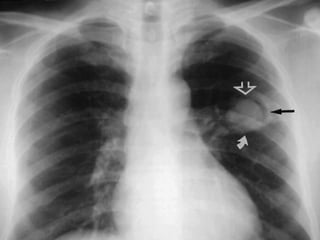

HAMPTON HUMP SIGN

• It is a wedge-shaped, pleura-based consolidation with a

rounded convex apex directed towards the hilus.

• This sign was first described by Aubrey Otis Hampton.

• It is usually encountered at the lower lobes and heals with

scar formation

HAMPTON HUMP SIGN •It is a wedge-shaped, pleura-based consolidation with a rounded convex apex directed towards the hilus. • This sign was first described by Aubrey Otis Hampton. • It is usually encountered at the lower lobes and heals with scar formation

• #26 Occurs within two days as a result of alveolar wall necrosis accompanying alveolar hemorrhage due to pulmonary infarct. OCCURS MOST COMMONLY DUE TO PULOMONARY EMOBLISM AND LUNG INFARCTION . (vascular occlusion due to invasive aspergillosis) THE EXPECTED APEX OF THIS WEDGE SHAPED INFARCTION IS SPARED BECAUSE OF BRONCHIAL ARTERIAL CIRCULATION IN THIS PART,resulting in the characteristic rounded appearance of a hampton hump . \occlusion occurs secondary to heamarrhoage due to dual blood supply fron the bronchial arteries . In case of infarction. It takes months to resolve and often leaves a linear scar . If the underlying parenchyma dosent undergo infarction , the hsmption humo will resolve within a week keeping its typical configuration – MELTING SIGN ,.